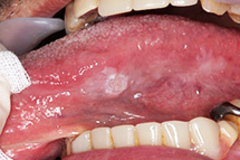

口腔癌の初期には以下のようなサインや症状が現れることがあります。

- 口腔内の潰瘍や白斑: 口腔内に白い斑点や潰瘍ができて、治らない場合は注意が必要です。